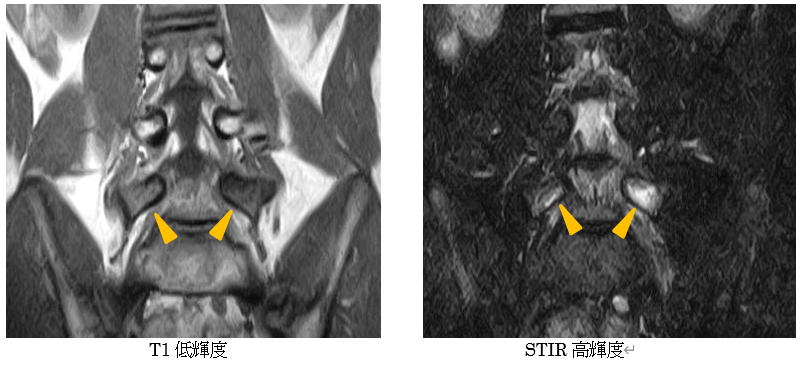

早期診断にはMRIが有用です。

上図MRIでは第5腰椎の椎弓部にT1強調像で黒く、STIR条件では白く変色している部分が疲労骨折の部分です。